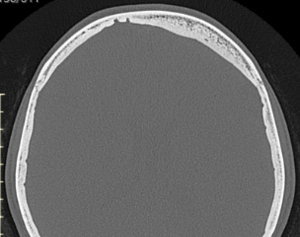

Aesthetic improvement of frontal bossing is achieved through bony reduction using burring or shaving of the frontal bone. In cases with fronto-temporal bossing, the bone reduction extends laterally toward the temporal bone, requiring contouring of the bony temporal line and sometimes partial removal or repositioning of the temporal muscle. The extent of achievable reduction depends on the thickness of the frontal bone, which must be evaluated preoperatively using a 3D CT scan.

This young female patient presented with congenital frontal bossing and a broad head shape. Childhood photographs confirmed that the condition had been present since infancy. Her primary concern was the size and convexity of her forehead, though she was not bothered by her relatively high hairline.

Frontal bossing with lateral head widening is congenitally determined and likely influenced by early brain growth patterns. It is not typically caused by excessive bone thickness; in fact, the bone may be thinner than average. Consequently, complete normalization of the forehead contour is rarely achievable, as the degree of reduction is limited by bone thickness—particularly over the upper forehead and along the temporal lines.